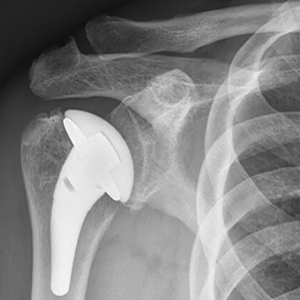

Shoulder Replacement

David is a 78 year old gentleman who enjoys ballroom dancing and being in the outdoors! He had debilitating arthritis and rotator cuff tears in both shoulders, and underwent reverse shoulder replacement four months apart. In the video below he is 6 weeks postoperative from right shoulder replacement and 6 months out from left shoulder replacement! Custom baseplates were used on both sides due to complex bony wear on the glenoid/socket, and through diligent rehabilitation he has already achieved an excellent result. Reverse shoulder replacement can get you back to the activities that you enjoy!